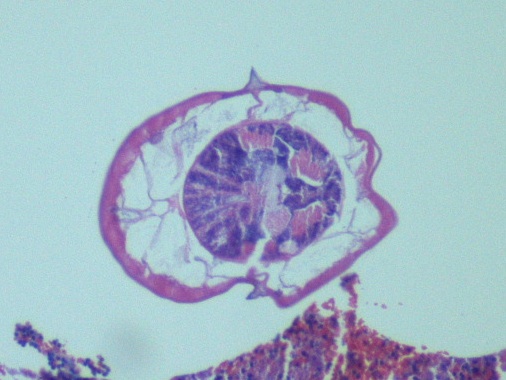

The bronchoscopy revealed a bloody fluid admixed with clots which was clinically consistent with diffuse alveolar hemorrhage. The roundworms depicted above were identified in both the BAL and stool O&P exam. Based on the presence of the short buccal cavity and the prominent genital primordium and the absence of eggs, the identification of Strongyloides stercoralis was made. Given the large amount of larvae present in both the lungs and gastrointestinal tract, the patient was diagnosed with a strongyloidiasis hyperinfection.

In the laboratory, the diagnosis of S. stercoralis is most often made by an ova and parasite exam of the stool, duodenal fluid, sputum or BAL specimens (Image 1). Most commonly the rhabditiform larvae are present and are identified by the presence of a short buccal cavity and prominent genital primordium (Image 2). These two features are helpful in distinguishing S. stercoralis from hookworms (Ancylostoma spp. and Necator americanus) which have a longer buccal cavity and indistinct genital primordium. The eggs of these two nematodes are also very similar, although typically S. stercoralis eggs hatch before they are passed in stool specimens. S. stercoralis can also be visualized on H&E histology sections in the crypts of intestinal biopsies where the adult female measures up to 2.2 mm in length. Finally, serologic testing can be helpful when there is a high suspicion of disease in the face of multiple negative stool exams, but cannot distinguish between a current or past infection. Most patients do not remember a specific exposure and prevention includes wearing gloves and shoes when handling or walking on soil that may contain contaminated fecal material. Treatment options for an acute or chronic S. stercoralis include a short course of ivermectin or albendazole. In the case of disseminated infection, ivermectin should be given until stool and sputum exams are negative for 2 weeks. In the case of our patient, she was started on ivermectin, but succumbed to the disease due to extensive pulmonary hemorrhage.